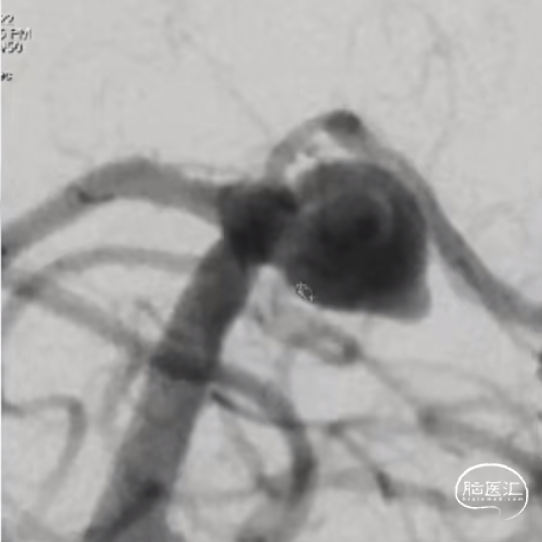

现病史:4天前,患者上厕所时出现爆裂样头痛、大汗淋漓、呕吐,未出现意识障碍、大小便失禁、四肢运动障碍、视力下降、视野缺失等症状,遂至当地社区医院就诊,予以输液治疗(具体不详)后自觉缓解,遂出院,1天前患者无明显诱因再次出现爆裂样头痛,较前加重,未出现意识障碍,大小便失禁等症状,遂至当地医院就诊,完善头颅CT、CTA检查提示:蛛网膜下腔出血,双侧大脑中动脉瘤(M1分叉前),左侧颞叶出血,予以对症治疗后,为进一步诊治,遂至我院,急诊以“颅内动脉瘤破裂伴蛛网膜下腔出血”收入我科。

经测量可得动脉瘤宽度平均值为9.1mm,动脉瘤最小高度为8.9mm,最终选择WEB™ SL 11*6。

WEB™经由VIA™微导管缓慢推送至微导管头端。缓慢推出WEB™从种子至萌芽状态,继续向瘤腔内远端缓慢推送WEB™至萌芽至开花间状态;将WEB™送至瘤顶,固定WEB™推送杆回撤VIA™,WEB™完全释放。

经造影可见WEB™尺寸合适,贴合瘤壁。解脱后,再次造影可见动脉瘤瘤腔内有明显造影剂滞留。WEB™对分支血流有影响,使用支架保护分支。

术后6个月随访造影,WEB™充分栓塞,瘤颈残留,WEB™被压缩。